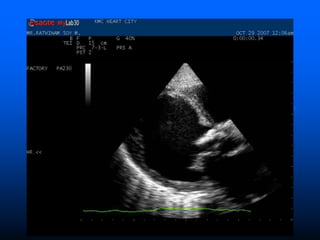

 Trans Thoracic Echocardiograpy (TTE)

– rapid, non-invasive – excellent specificity (98%) but

poor sensitivity

– obesity, chronic obstructive pulmonary disease and

chest wall deformities

 Transesophageal Echo (TOE)

– more invasive, sensitivity up to 95%, useful for

prosthetic valves and to evaluate myocardial

invasion

– Negative predictive valve of 92%